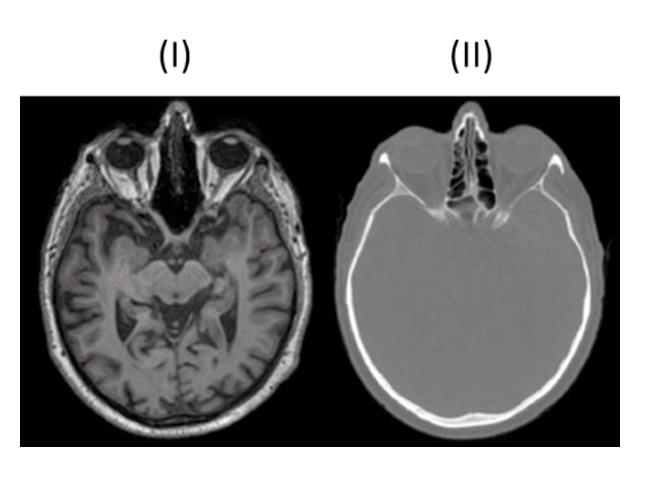

MRT (Bild I)

Strahlenfrei

hohe Bildqualität

Weichteildarstellung

Flexibilität bei Schnittführung

MRT (Bild I) typische Merkmale

Erzeugung Graustufenbildern basierend auf Anregung der Wasserstoffprotonen im Gewebe

T1-Wichtung: Hervorhebung fetthaltiger Strukturen → Knochen schwarz, Fettgewebe weiß

T2-Wichtung: Hervorhebung wasserhaltiger Strukturen → Liquor weiß, weiße Substanz dunkelgrau

CT (Bild II)

CT (Bild II) typische Merkmale

Weniger Kontrast bei Weichgewebe

Weiße Knochen

Der lineare Schwächungskoeffizient µ der Lunge für diagnostische Röntgenstrahlung beträgt aufgrund der niedrigen mittleren Dichte des Gewebes nur circa 30% des Wertes µ für Wasser. Berechnen Sie hieraus den mittleren Hounsfield-Wert von Lunge in einem CT-Bild.

-700 HU